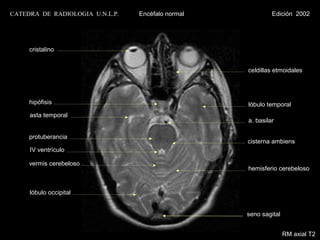

CATEDRA DE RADIOLOGIA U.N.L.P.   Encéfalo normal            Edición 2002

cristalino

celdillas etmoidales

hipófisis                                     lóbulo temporal

asta temporal

a. basilar

protuberancia

cisterna ambiens

IV ventrículo

vermis cerebeloso

hemisferio cerebeloso

lóbulo occipital

seno sagital

RM axial T2